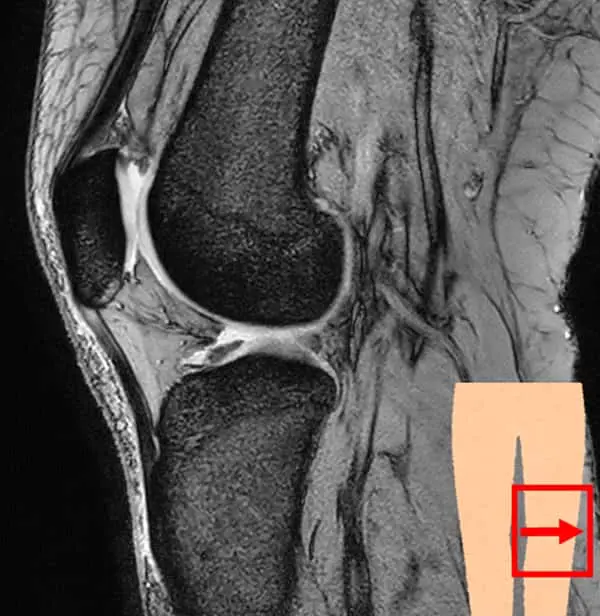

膝関節は大腿骨(太ももの骨)と脛骨(すねの骨)、腓骨(脛骨の外側にあるすねの骨)、膝蓋骨(膝のお皿)から構成されています。これらの骨を靱帯や筋肉、腱で繋いでおり、それらによって安定性を保っています。

膝関節の検査では、レントゲンの検査が一般的ですが、当クリニックではMRIを使用した検査を行なっています。

レントゲンよりも骨の内部や軟骨、半月板・靱帯の状態を把握できます。また、炎症や水が溜まっているかなどの確認も可能です。レントゲンとは違い、放射線被ばくもなく検査ができますので、体への負担が気になる方にもおすすめです。